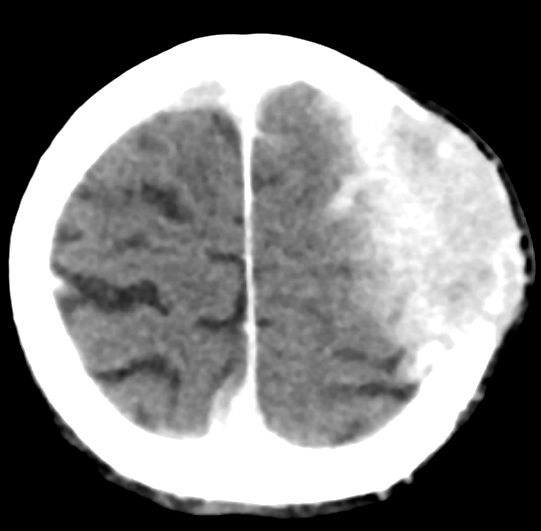

| CT: multiple Hirnmetastasen | Adenokarzinom der Lunge. CT-Untersuchung des Hirns mit Kontrastmittel. | |||